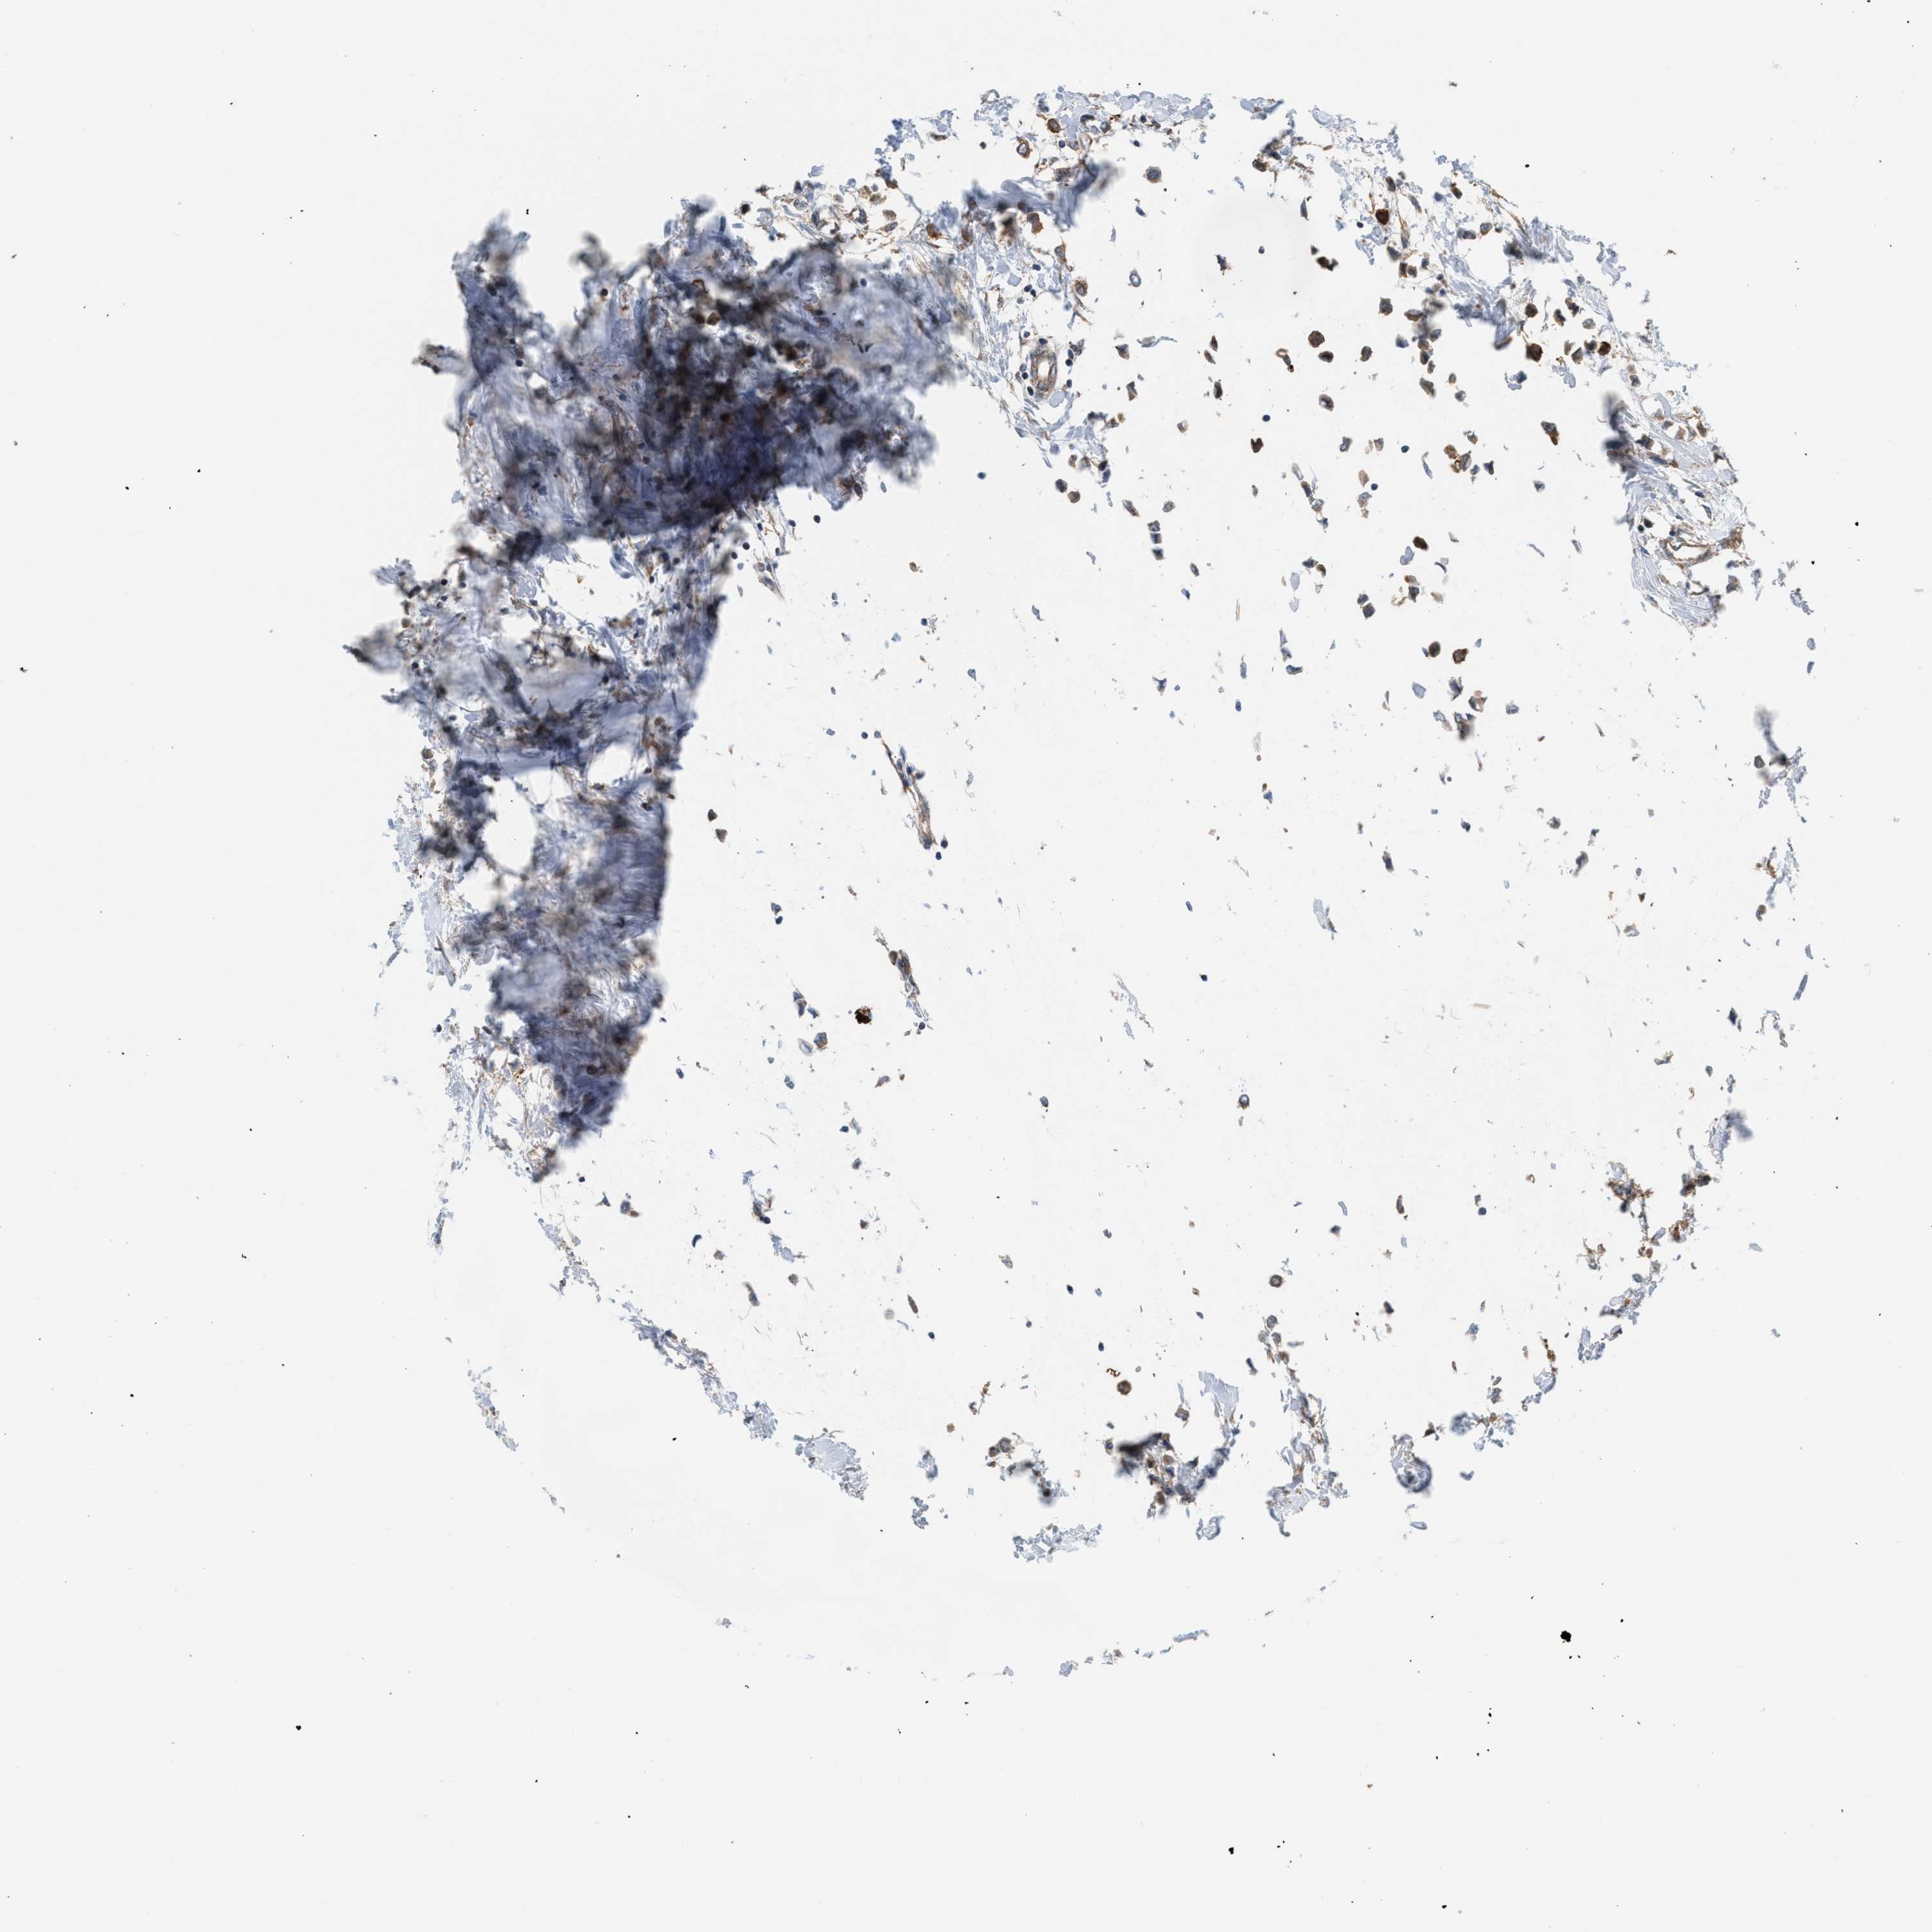

CANCER BREAST CANCER Show tissue menu

BRCA TCGA BRCA VALIDATION PROTEIN EXPRESSION

ANTIBODIES

AND

VALIDATION